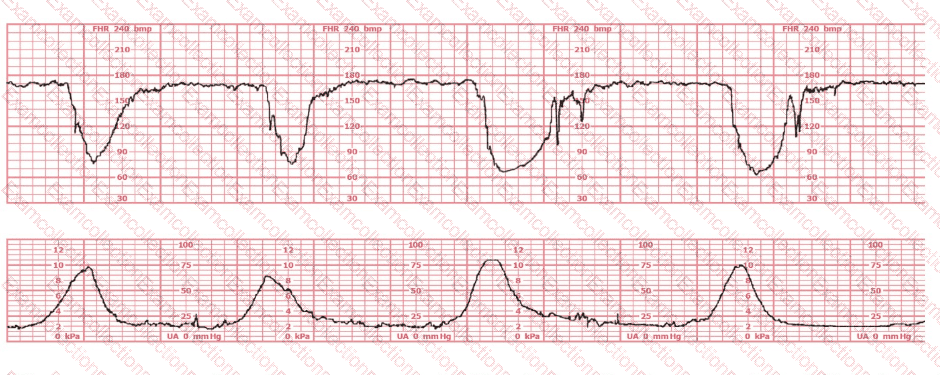

This fetal heart rate tracing is of a woman in labor with dichorionic-diamniotic twins at 36-weeks gestation, 4 cm dilated. She is on oxygen via face mask. Based on the fetal heart rate tracing, what is the most appropriate action?

(Tracing A = black; Tracing B = blue)